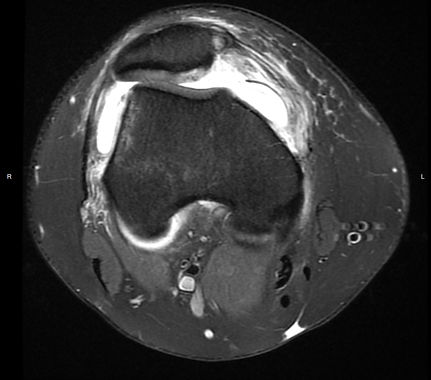

MPFL tear on MRI

The MPFL, or Medial Patellofemoral Ligament, is the ligament keeping the kneecap, or patella, from dislocating. The MPFL stabilizes the kneecap, and when a kneecap dislocation occurs, the MPFL may tear or become stretched out. Without a competent MPFL, the kneecap can recurrently dislocate.

This injury can occur for a variety of reasons: a plant-and-twist (pivot) injury, or a fall or trauma. An examination in the office as well as MRI imaging will confirm the presence of a torn MPFL or any cartilage injuries to the underside of the kneecap. Treatment depends on the severity of the injuries found: